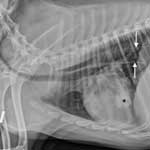

Диагноз. Диагноз на пневмонию ветеринарный специалист клиники ставит комплексно на основании симптомов болезни, проведения лабораторного исследования крови и мочи. Общий анализ крови дает нейтрофильный лейкоцитоз с сдвигом влево, количество эритроцитов и гемоглобина уменьшается. В обязательном порядке больной собаке делается рентгенография и рентгеноскопия легких, на рентгенограмме видны участки затемнения. Рентгенологическое обследование грудной клетки должно проводиться в двух проекциях. Для исключения пневмоний паразитарного происхождения проводят исследование кала на гельминты.

Сделали рентген легких, по которому предположили пневмонию.

Описание рентгеновских снимков от 28.09.2017: Тень сердца не увеличена, трахея не смещена. Альвеолярная инфильтрация во всех долях легких, контуры сердца и диафрагмы нечеткие. Край печени притуплен, выступает за последнее ребро. Заключение: — пневмония (некардиогенный отек легких ?); — гепатомегалия.

Описание рентгена от 05.10.2017: Сохраняется альвеолярная инфильтрация во всех долях легких. Признаки течения пневмонии, минимальная положительная динамика. Гепатомегалия.

Описание рентгеновских снимков от 21.10.2017: Сохраняется альвеолярная инфильтрация во всех долях легких без динамики. Дифф. диализ: — течение пневмонии; — диффузный тип опухолевого процесса; — некардиогенный отек легких. Гепатомегалия. Без динамики.